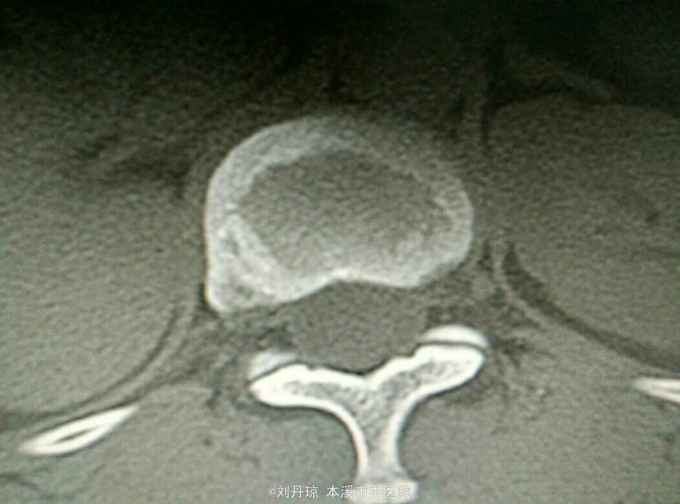

腰部疼痛伴右下肢放射痛麻木感1年,加重1月。患者1年前劳累后感到腰部疼痛伴右下肢放射痛麻木感,近1月病情加重来诊。

查体:L3—S1棘突右旁压痛阳性。直腿抬高实验左70度,右40度。 直腿抬高加强实验左侧阴性,右侧阳性。腰椎功能障碍。 辅查:CT: L3—S1椎间盘突出。